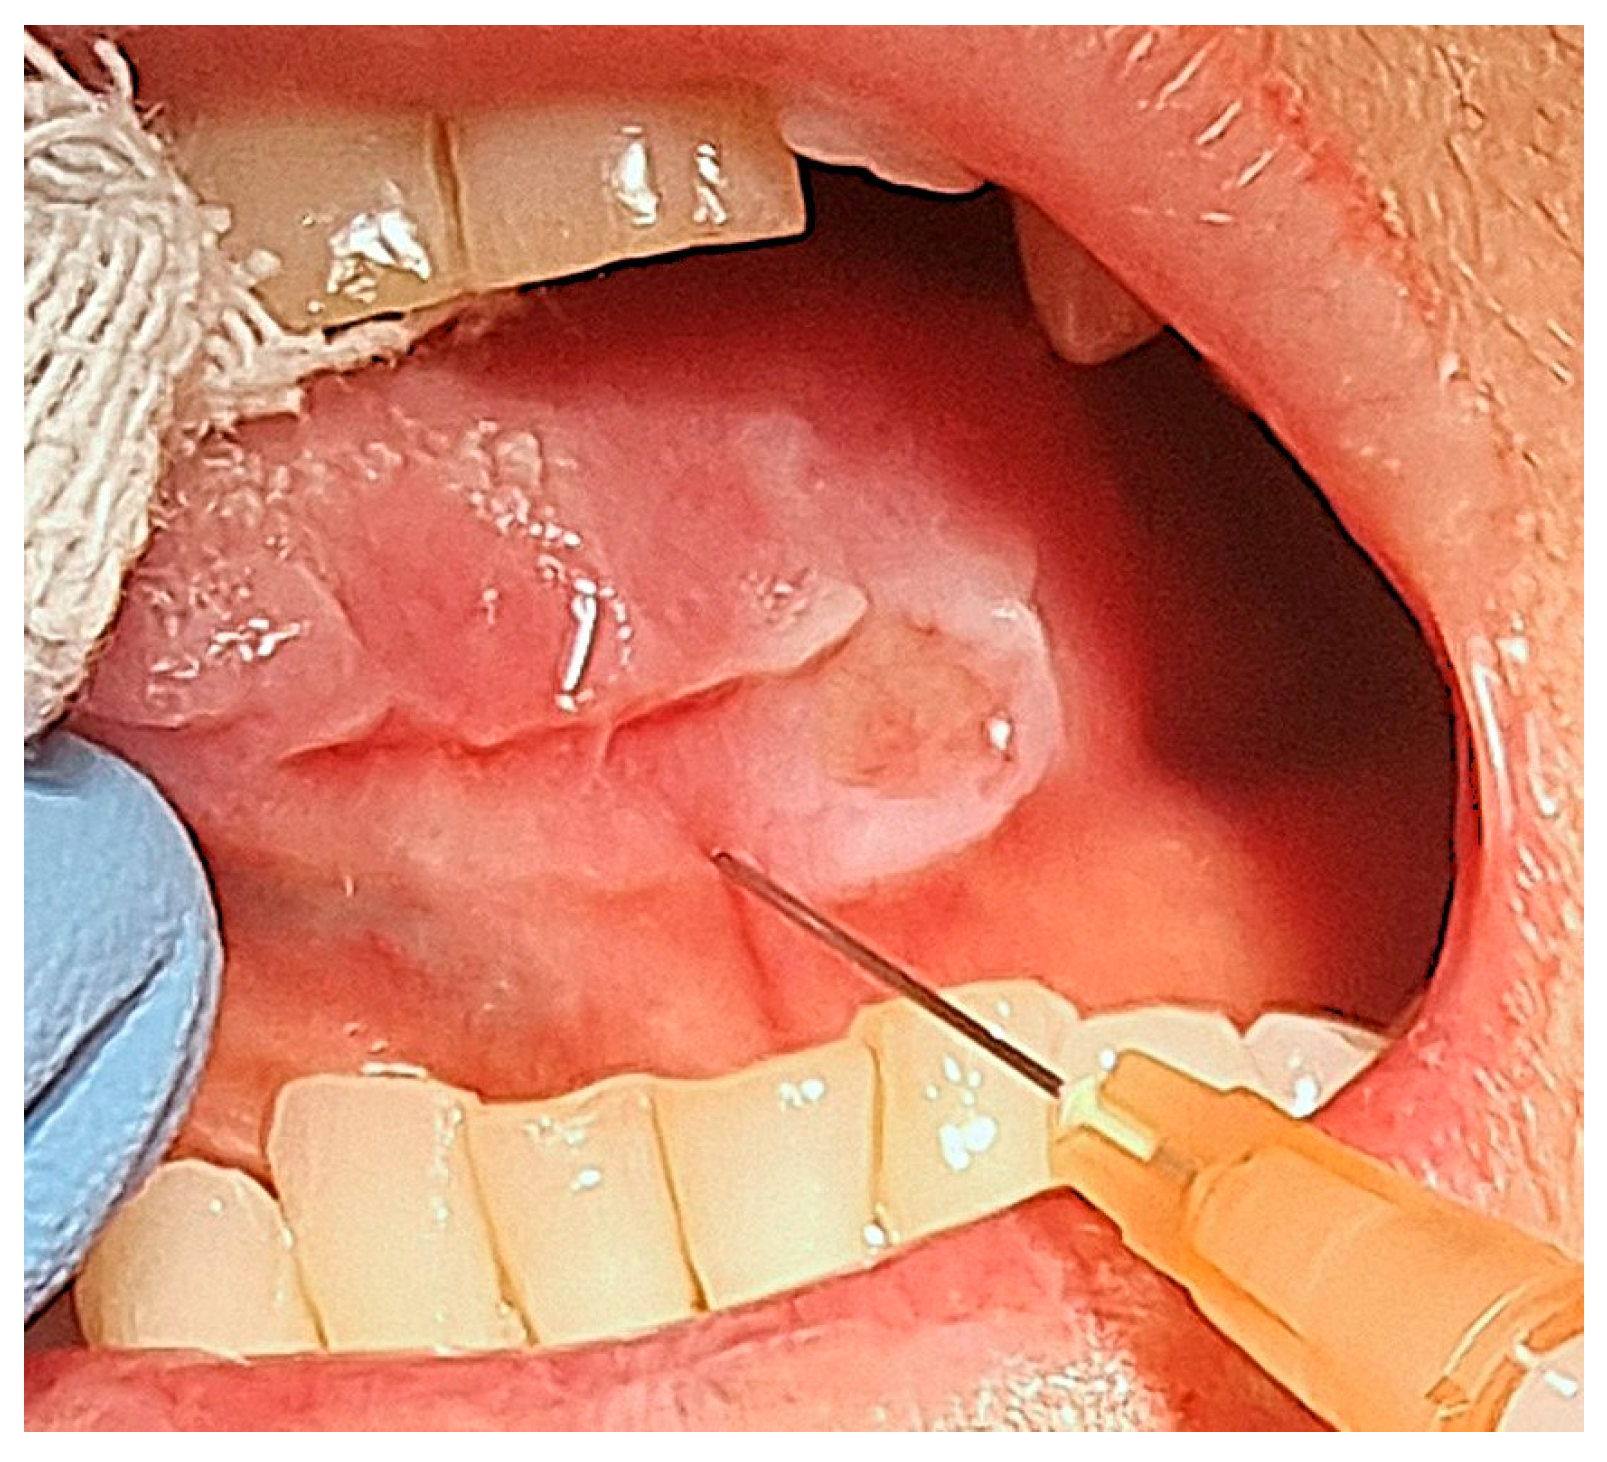

Case Treatment

3. Results